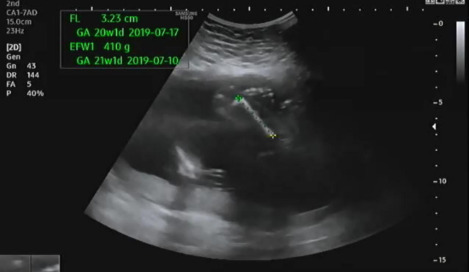

그다음 허벅지와 팔 길이를 측정하는데 다행히 전체적으로 주수에 알맞게 성장 중이라고 의사가 설명했다.

허벅지 길이를 측정하고 아래를 보면 발가락의 개수를 확인했다. 양측 모두 다 발가락 5개 있는지 확인했다. 초음파를 보는데 햇님이가 불편한지 여기저기 발로 밀어대는 모습을 볼 수 있었다.